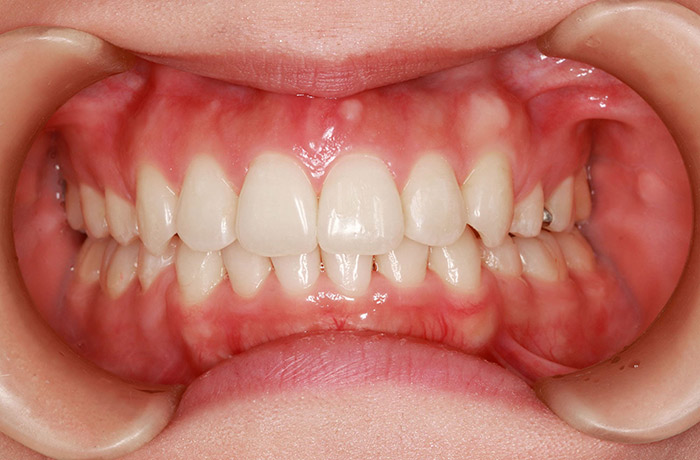

治療後

after

患者の症状 叢生、正中のずれ、上顎左右側切歯の口蓋側転位(交叉咬合)

治療方法 非抜歯で、マウスピース型カスタムメイド矯正歯科装置(インビザライン)による矯正

歯列弓を拡大することで非抜歯を可能にしました。

治療結果 側切歯の交叉咬合は解消、上下正中のずれも改善し咬み合わせが良くなりました。